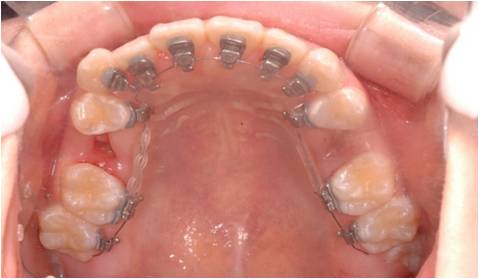

설측교정장치

치아 안쪽에 장치를 붙여 겉으로는 전혀 보이지 않는 장치입니다.

겉으로 보이지 않아 심미적이지만 외부노출 장치와 달리 초기에 약간의 이물감과

발음장애가 일시적으로 있을 수 있습니다.

대부분의 설측교정 환자들은 1,2주 이내에 적응이 되어 점차 이물감이 없어지며, 설치음(ㄷ,ㅌ,ㅅ)이 장애를 받지만 수주 내에 적응이 되며 쉽게 적응이 되지 않는 경우라 해도 본인의 연습을 통해 해결될 수 있습니다.